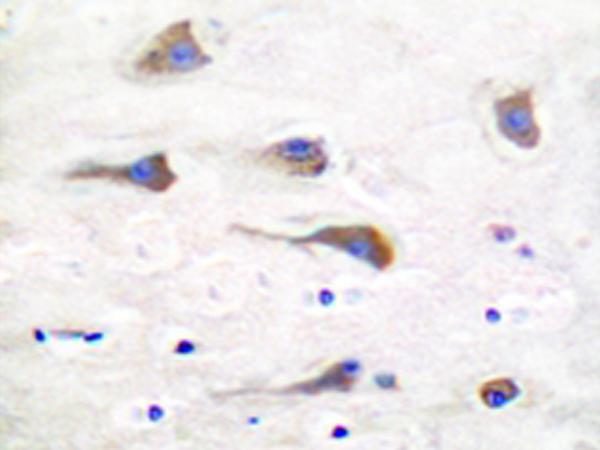

IHC positive control:

Human brain tissue

IHC Recommend dilution:

50-100